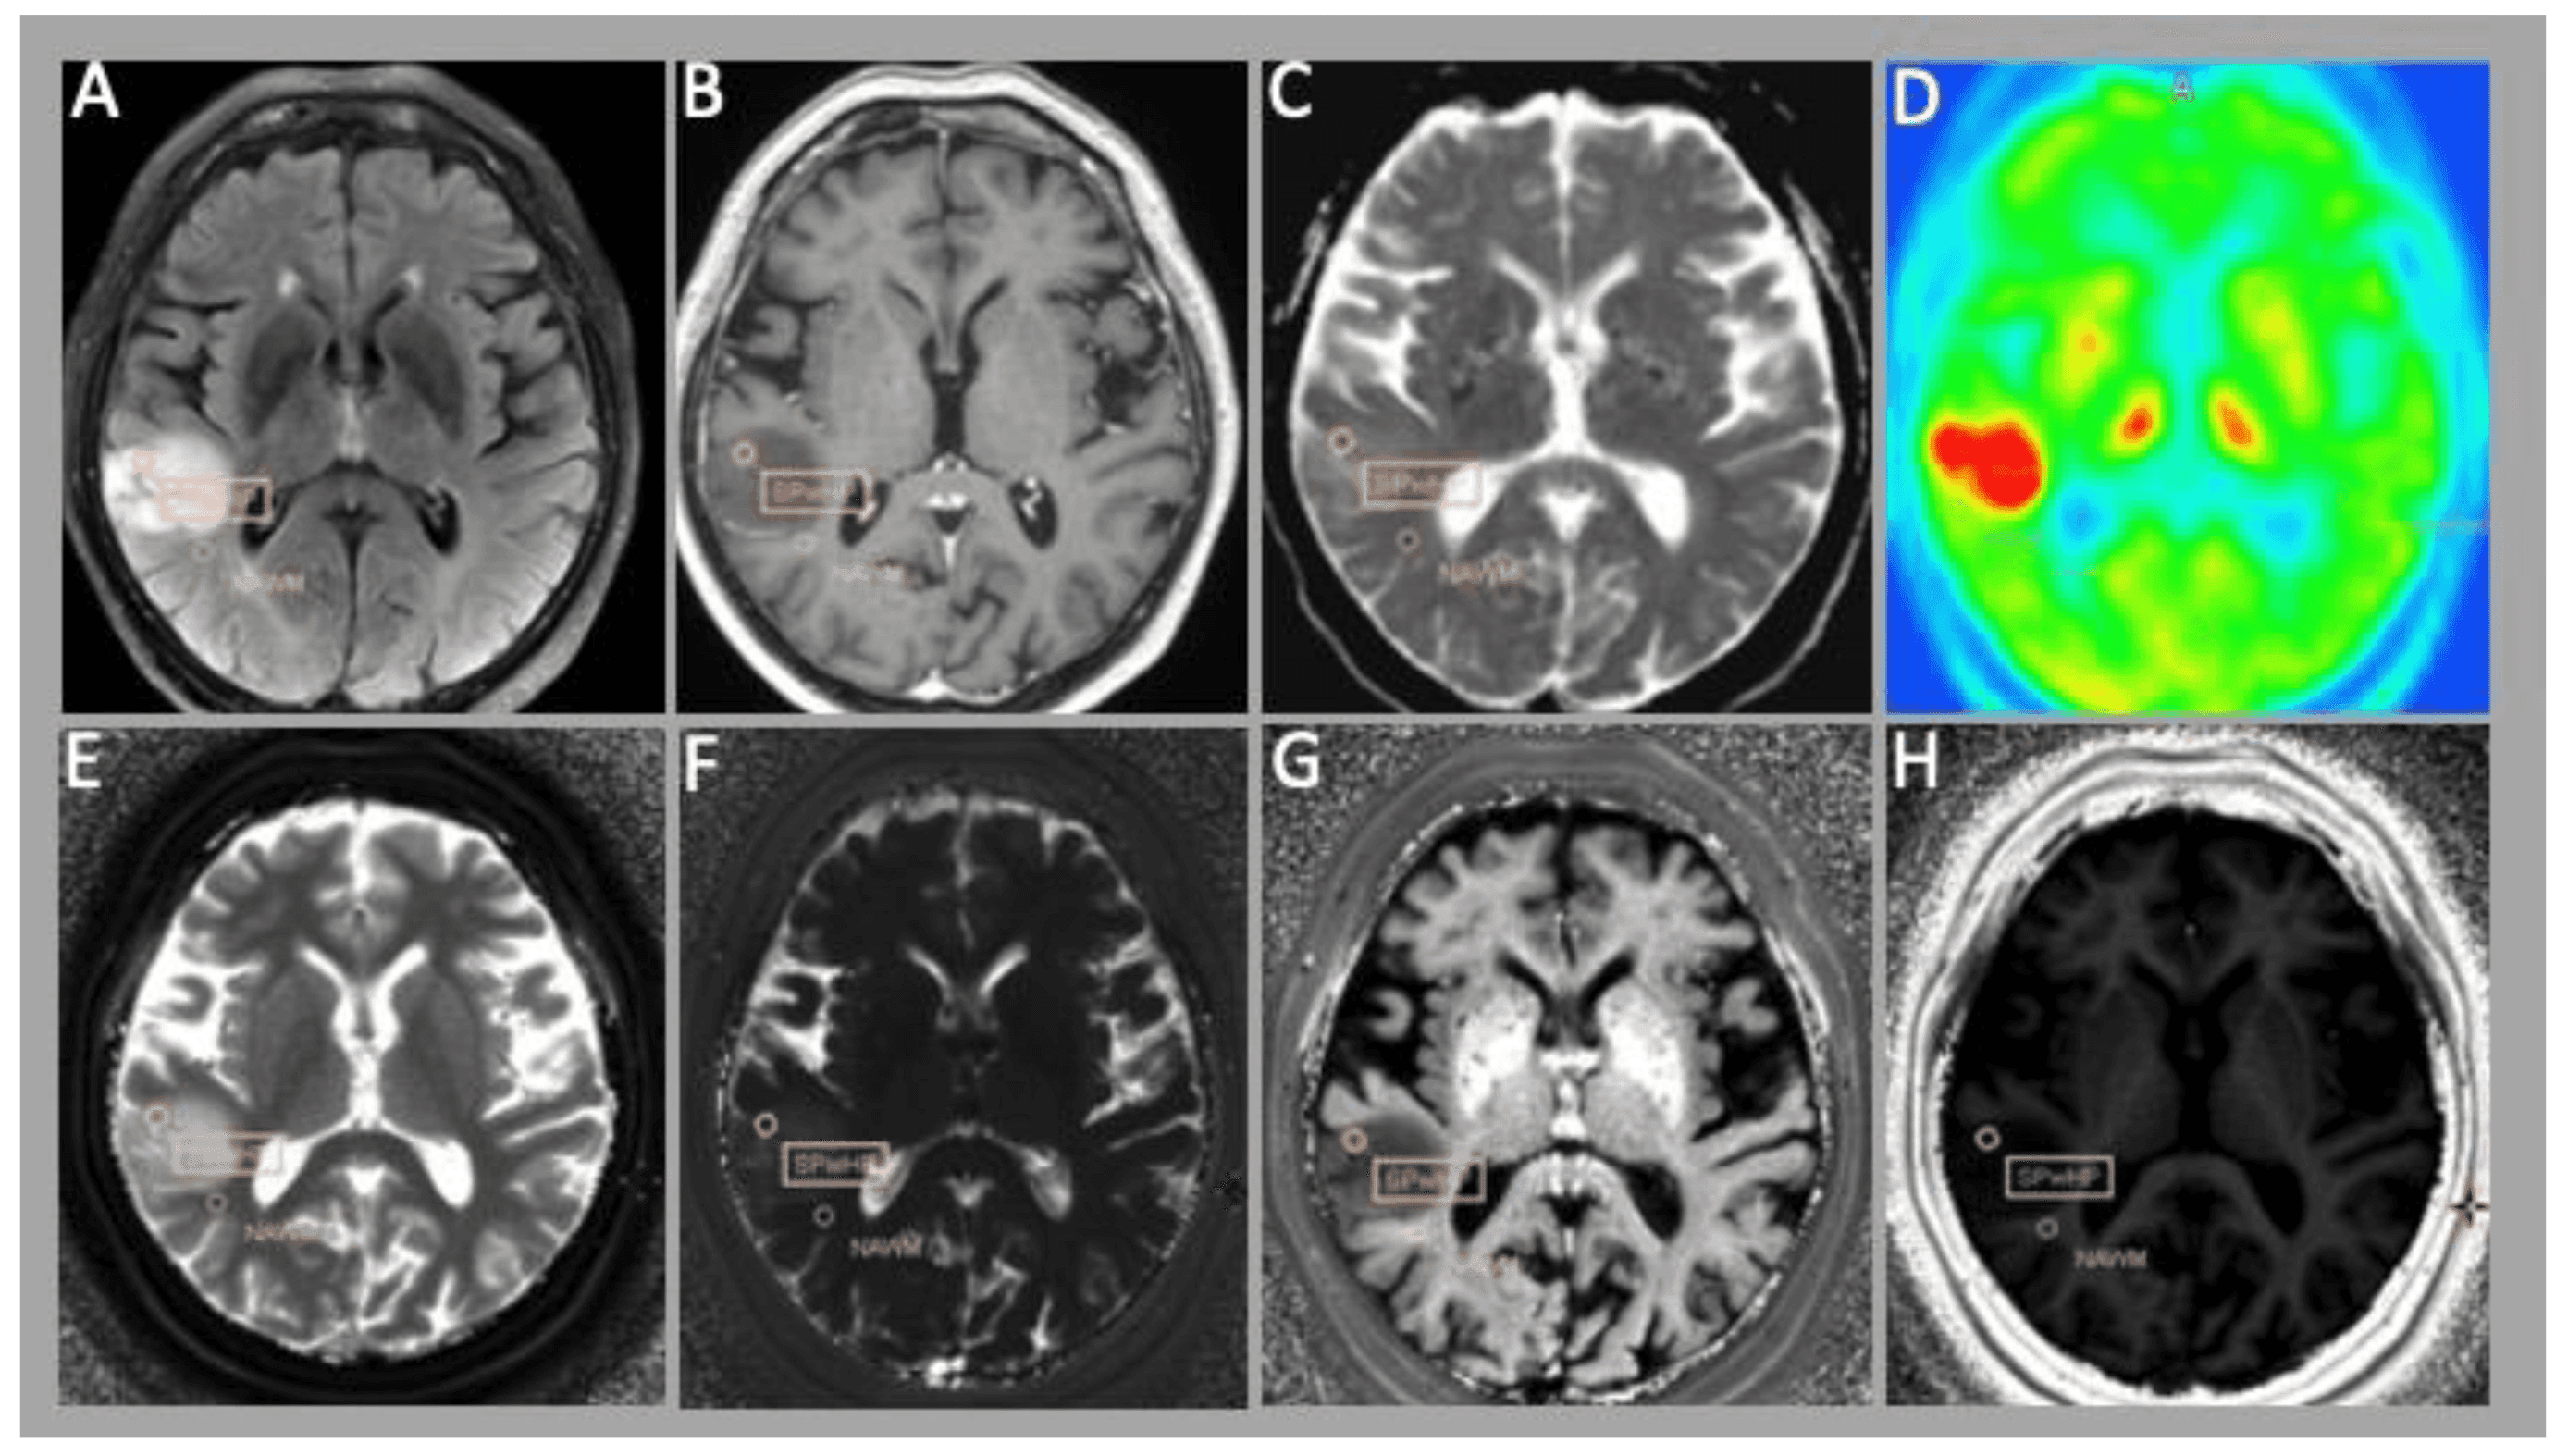

Gliomas are complex brain tumors that require individualized treatment. Imaging techniques such as MRI and PET have their limitations, both in diagnosis and in monitoring the course of treatment. Frequently, invasive procedures are needed to determine the tumor. This is the subject of the new collaborative doctoral program of the Medical University of Vienna and the University of Applied Sciences Technikum Wien, which is funded by the Austrian Science Fund FWF.

Photo material: an example image from the data set can be found at https://cloud.technikum-wien.at/s/aofBy8kRnPPWgoG (Edited from DOI: 10.3390/cancers15102740, licensed under CC BY 4.0.)